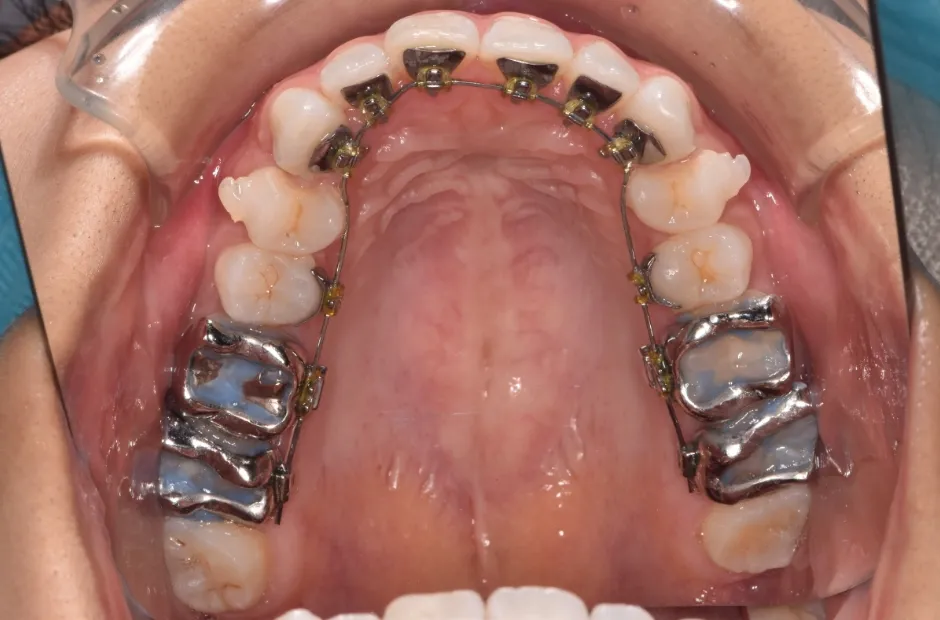

治療中

叢生

| 診断名・主訴 | 叢生 |

|---|---|

| 年齢・性別 | 43歳・女性 |

| 治療期間・回数 | 2年7か月 27回 |

| 治療に用いた主な装置 | 舌側矯正 |

| 抜歯部位 | 両顎4,4 |

| 治療費 | 100万円(税抜) |

| リスク・副作用 | 装置による違和感・疼痛・歯肉退縮・歯根吸収・虫歯のリスクなど |